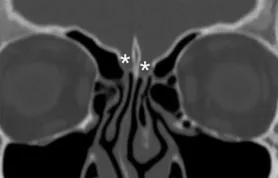

Coronal plane image of cribriform plate (asterisks).

Optic canal (asterisks) and superior orbital fissure (arrow)